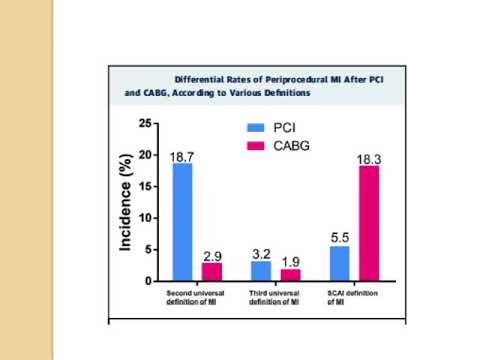

Significación clínica del infarto periprocedimiento. Dra. María Laura Estrella. Residencia Cardiología. Hospital C. Argerich. Buenos Aires